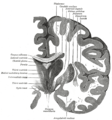

| رسم توضيحي لمسار ألياف lemniscus; medial lemniscus بالأزرق, lateral بالأحمر. | ||